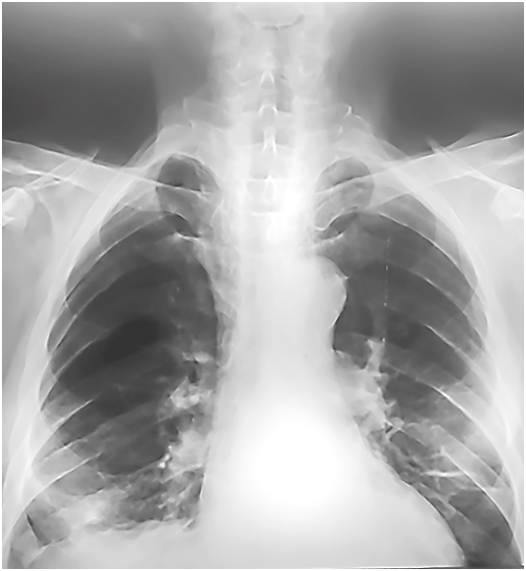

Послеоперационный период без осложнений. Наступила реаэрация правого легкого (рис. 7). Пациент выписан на 9-е сутки.

Рис. 7. Обзорная рентгенограмма грудной клетки в прямой проекции на 1-е сутки после операции.

Fig. 7. Chest X-ray (frontal projection) on the 1st postoperative day

Осмотрен через 6 месяцев. Жалоб не было. Дыхание в легких симметричное, без хрипов. Стул ежедневный. На обзорной рентгенограмме правое легкое воздушное, занимает весь гемиторакс (рис. 8).

Рис. 8. Обзорная рентгенограмма грудной клетки в прямой проекции через 6 месяцев после операции. Правое легкое полностью заполняет правый гемиторакс

Fig. 8. Chest X-ray (frontal projection) in 6 months after operation. The right lung completely fills the right hemithorax